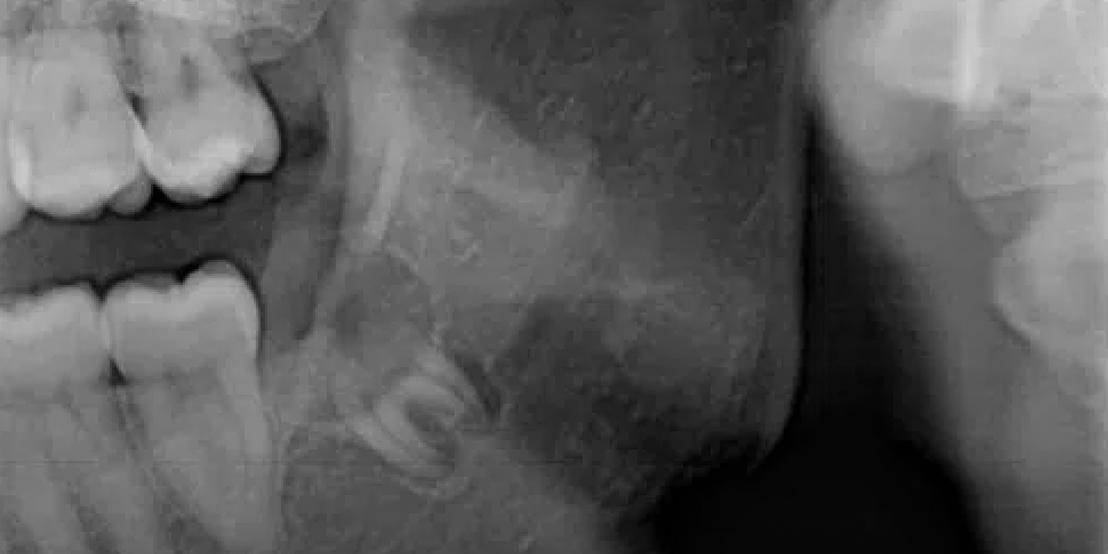

Wisdom Tooth Removal

Whether you need a dental filling Dubai treatment for decay or a dental gap filling to improve aesthetics and bite alignment, our gentle, expert approach protects your teeth and relieves discomfort. We also provide care for wisdom teeth, including safe and effective wisdom tooth extraction Dubai when needed. Count on us to keep your smile healthy, resilient, and looking its best for years to come.